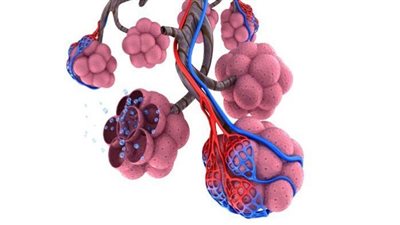

ما هي أعراض النفاخ الرئوي؟.. النفاخ الرئوي أو ما يسمى انتفاخ الرئة هو اضطراب تنفسي مزمن يؤدي إلى فقدان مرونة أنسجة الرئة وتلف الحويصلات الهوائية، مما يعوق التبادل الطبيعي للغازات ويؤدي إلى احتباس الهواء في الرئتين وصعوبة في التنفس، خاصة أثناء الجهد البدني، فهيا نتعرف خلال هذا التقرير على ما هي أعراض النفاخ الرئوي؟.